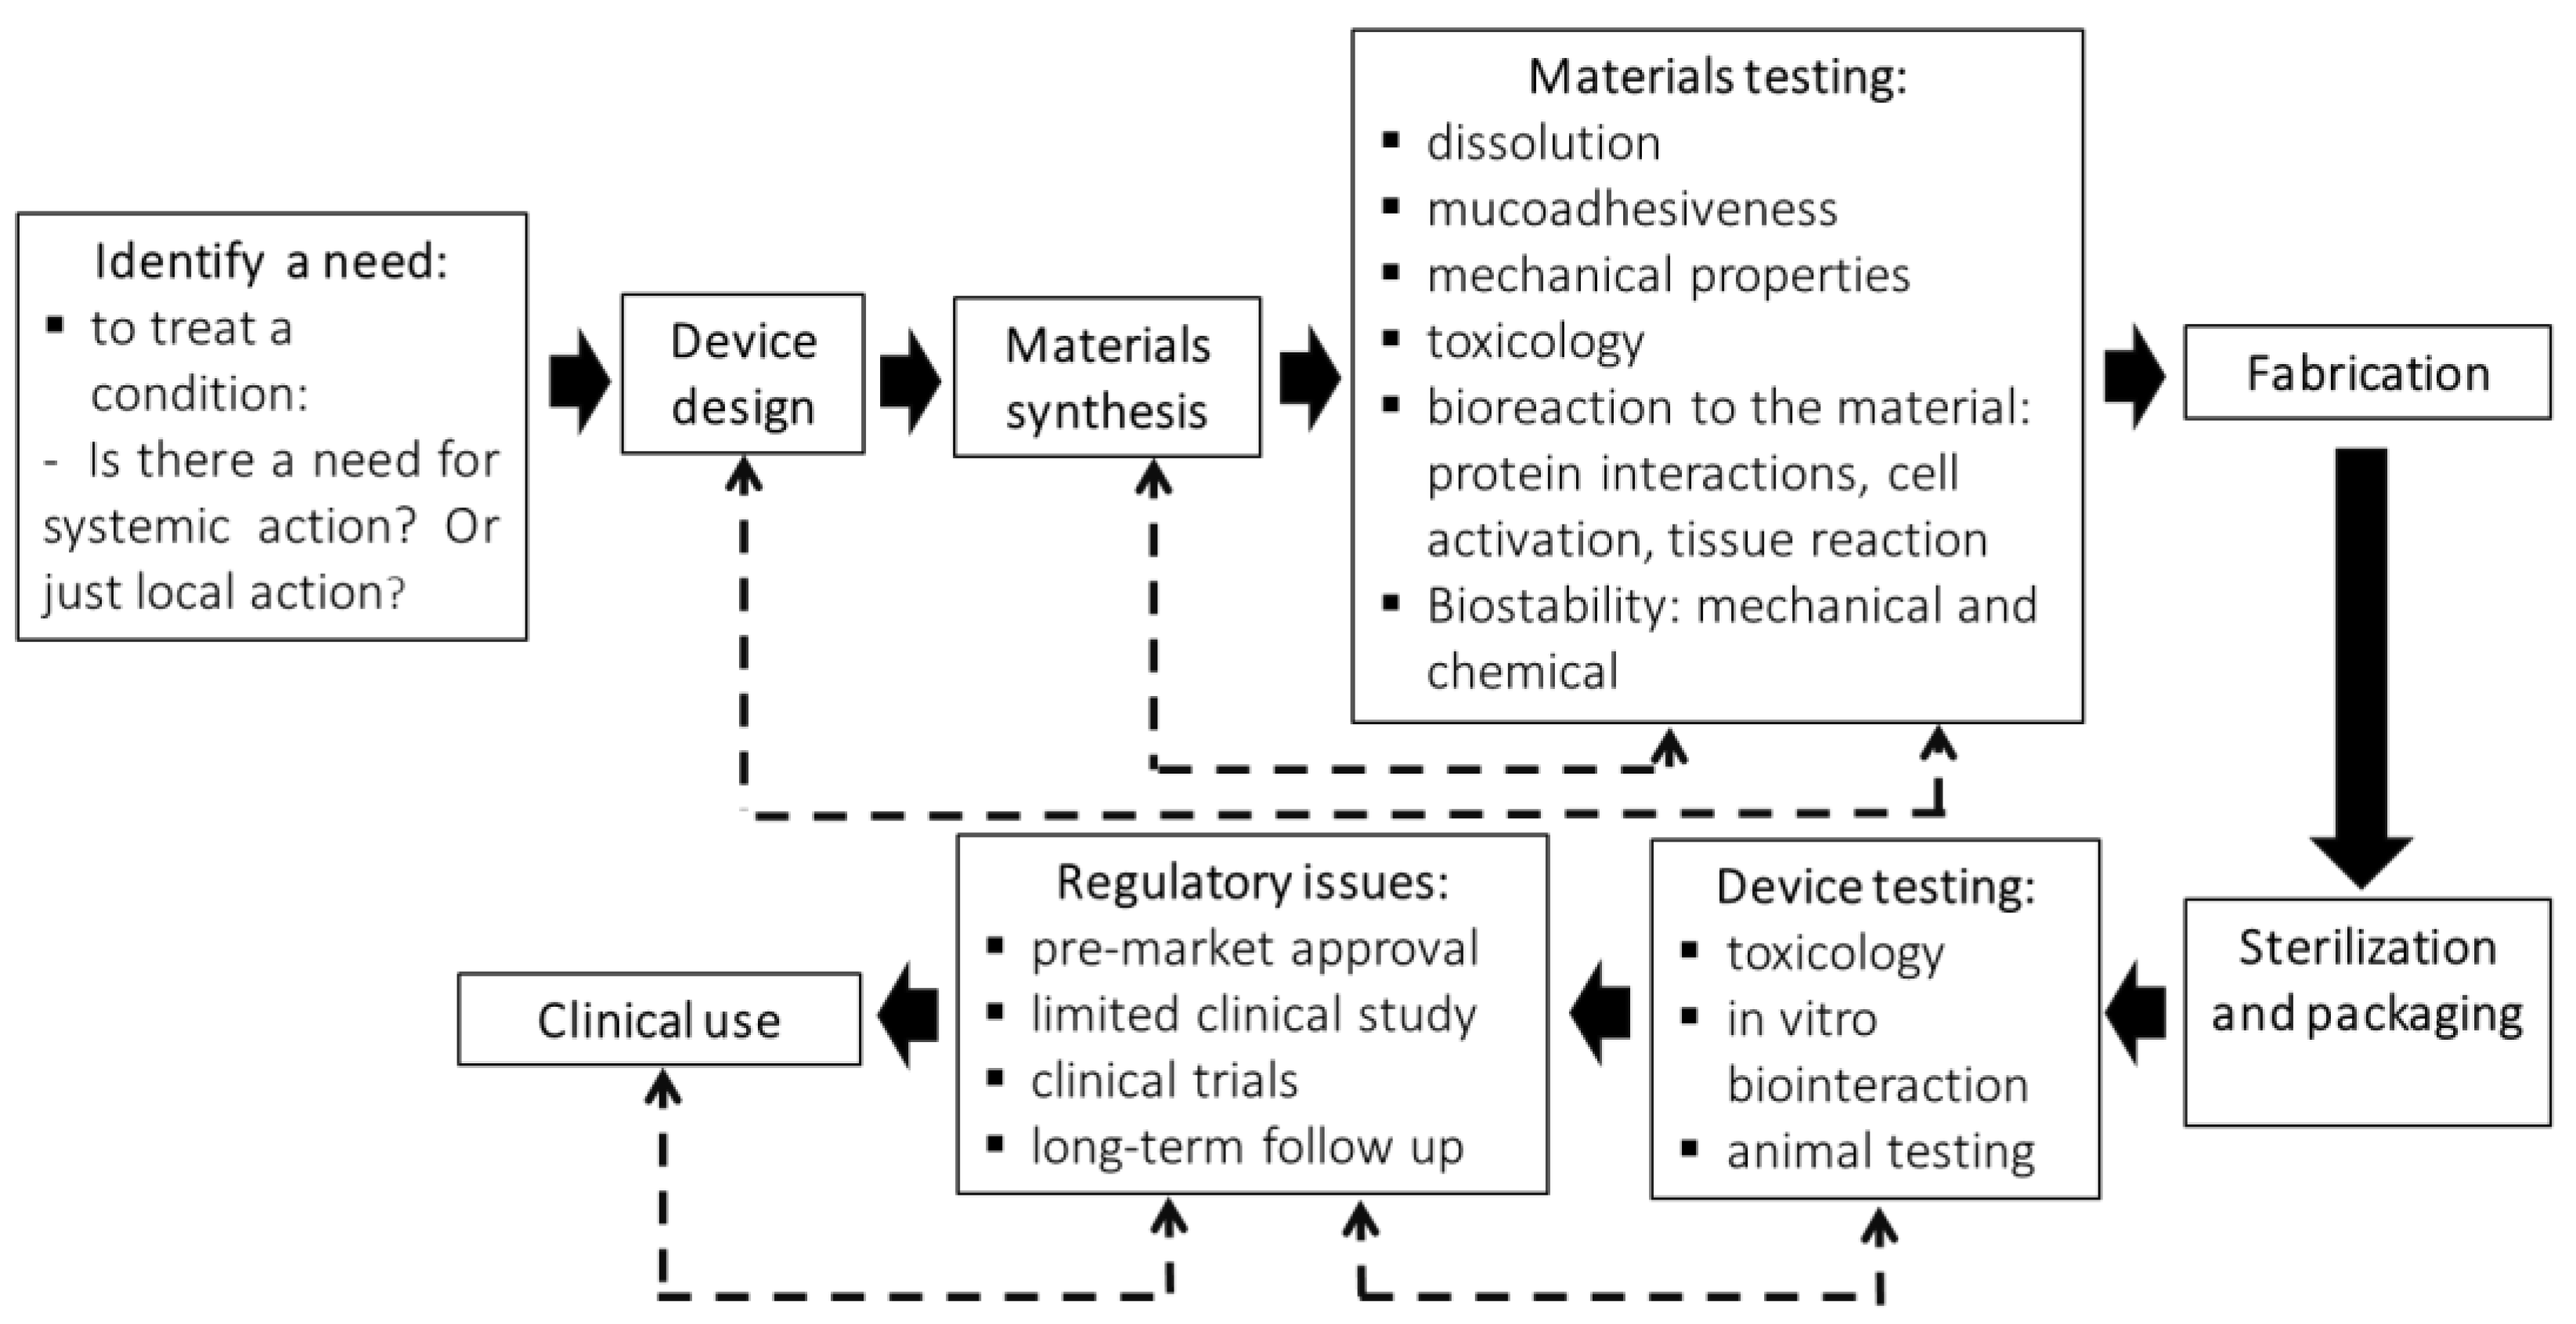

3. Steps Involved in the Production of an Oral Dispositive to Drug Delivery